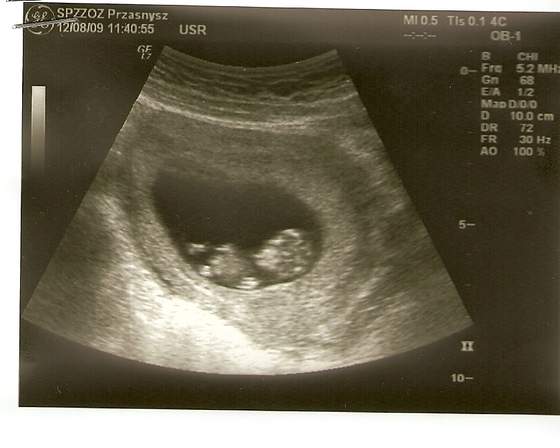

Hej dziewczynki a to moja dzidzia według usg 8 tydzień![]()

Mój Dziubasek